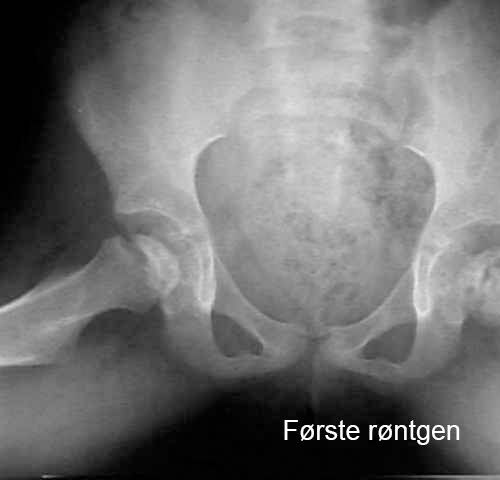

Lårbeinshodet dør delvis eller helt. Kroppen forsøker å løse dette ved å danne nytt beinvev og bryte ned det døde vevet. Det nye beinet er fortsatt svakt, noe som kan føre til at hoften mister sin runde form eller kollapser. Dette fører til deformasjon av hofteleddet. Bildene viser utviklingen av hoften hos et barn med Calvé-Legg-Perthes sykdom.